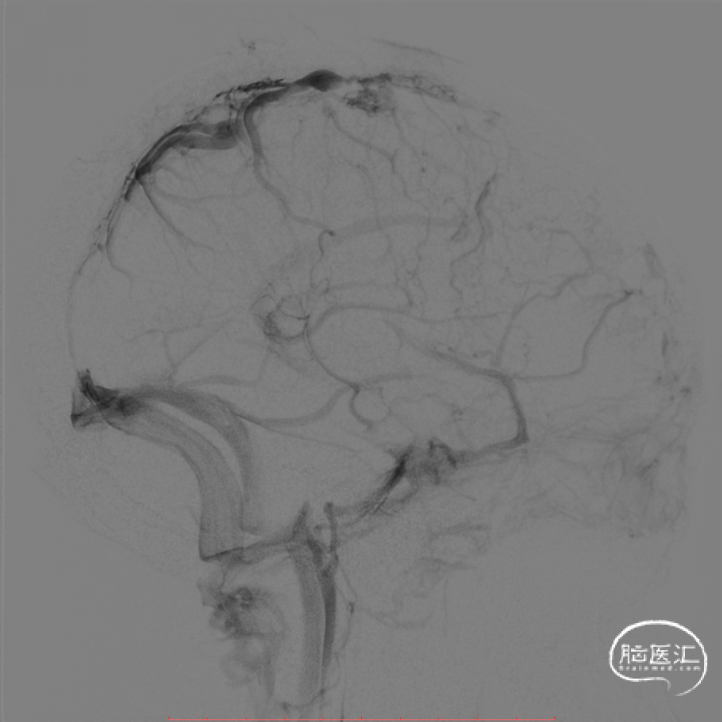

患者取仰卧位,全麻下右侧股动脉穿刺置入6F血管鞘,全身肝素化。5F单弯在泥鳅导丝引导下行全脑血管造影,可见静脉期上矢状窦断续显影且纤细,皮层静脉扩张瘀滞,右侧横窦、乙状窦显影不佳。

造影见上矢状窦中下段、窦汇、右侧横窦显影显影明显改善,上矢状窦前段显影仍欠佳。

复查造影见上矢状窦显影改善,皮层静脉扩张瘀滞明显减轻,窦汇处见明显充盈缺损。

再次经微导管释放取栓支架于窦汇处,下拉并经抽吸导管抽吸,抽吸导管逐渐下撤并一路抽吸至颈静脉孔,下撤长鞘,复查造影见上矢状窦、窦汇、右侧横窦、乙状窦显影改善。